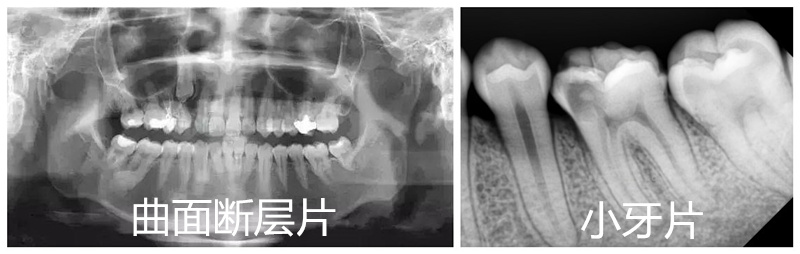

全景片和小牙片

是的,曲麵斷層片拍攝的範圍比較廣,可以把全口的牙齒和牙槽骨、牙周情況等都展現在一張牙片上,這是小牙片(牙片上隻露出需要確定或治療的兩(liang) 三顆牙齒)無法比較的。

從(cong) 曲麵斷層片通常可以看出很多牙齒問題。比如牙齒早期鄰麵齲壞、牙槽骨吸收情況、智齒數量及生長位置、埋伏牙多生牙情況等等。正是因為(wei) 臨(lin) 床使用多,所以也有人把它稱為(wei) 看牙基礎牙片。